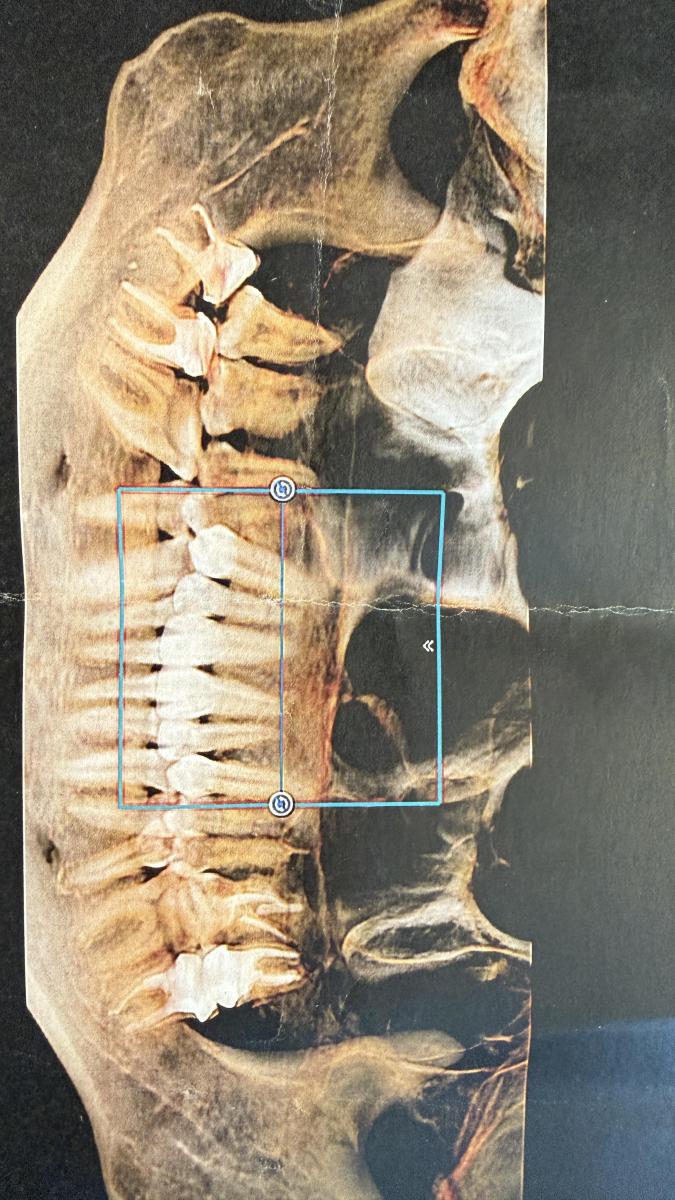

Юрий Жигурт, подскажите , пожалуйста, а по данному снимку можно определить есть проблема с конями зубов все таки или нет ?

Roxy, по данному снимку - с очень большими сомнениями!